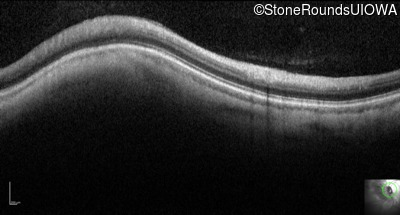

Optical Coherence Tomography - Left - 20/100

Exemplar